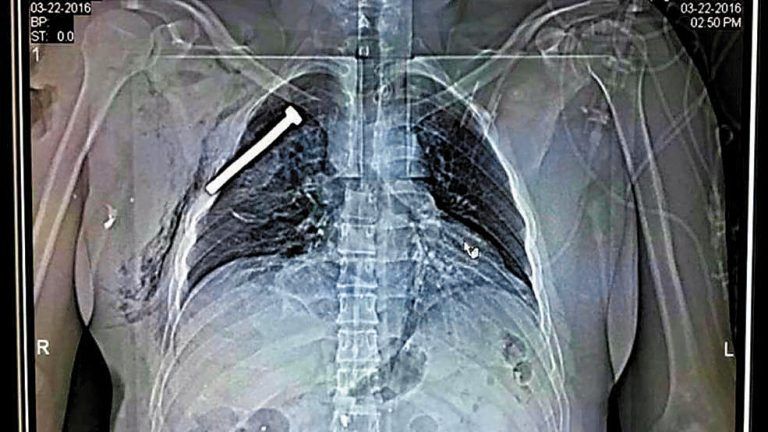

Bombe. Diese Aufnahme einer Brust, in der eine große Schraube steckt, stammt von einem bei den Anschlägen auf dem Flughafen verletzten Patienten, der in einem Militärkrankenhaus behandelt wird. Das Bild beweist, dass die Attentäter am Flughafen mindestens eine Nagelbombe gezündet hatten. In einem Gebäude in der Gemeinde Schaerbeek fanden Ermittler neben einer IS-Flagge einen Sprengsatz mit Nägeln und chemischen Substanzen.